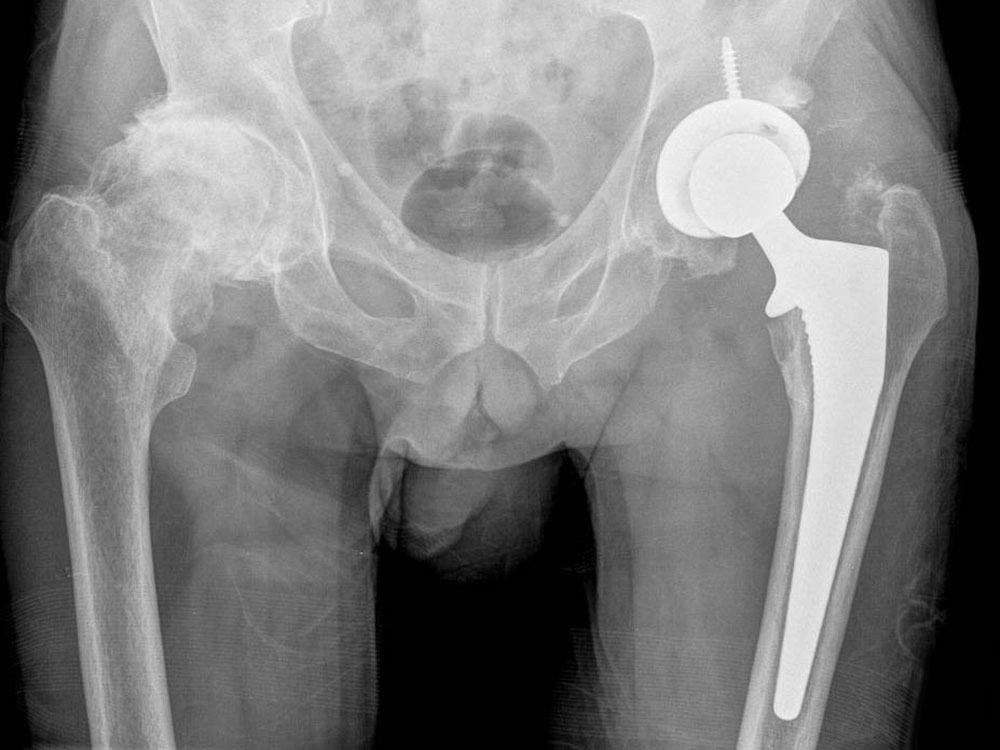

Premium Photo Total hip arthroplasty, xray image very good quality

Premium Photo Total hip arthroplasty, xray image very good quality Total Hip Arthroplasty Before Surgery They’ll replace the top (femoral head) of your thighbone (femur) and. Hip replacement is a reliable treatment for those whose hip arthritis has progressed beyond the help of nonsurgical treatments. A surgeon will replace your whole hip with a prosthetic joint. Components of the total hip replacement: It’s a common treatment for late stage osteoarthritis and other conditions. Hip replacement. Total Hip Arthroplasty Before Surgery.